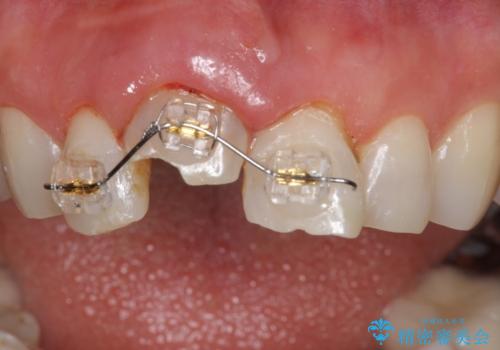

検査の結果、歯は大きく折れておらず、骨の中に埋め込まれていた状態であったため、部分矯正で歯を引っ張り出していきます。

ぶつけて埋まってしまった歯は、場合によって矯正治療で引っ張り出すことで保存することができます。